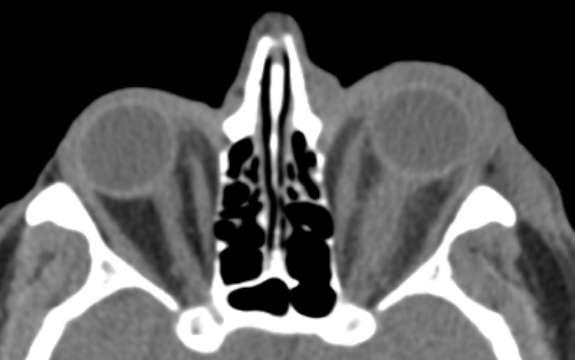

TAC (imagen B): Tumor de cuerpo carotídeo derecho, shamblin III